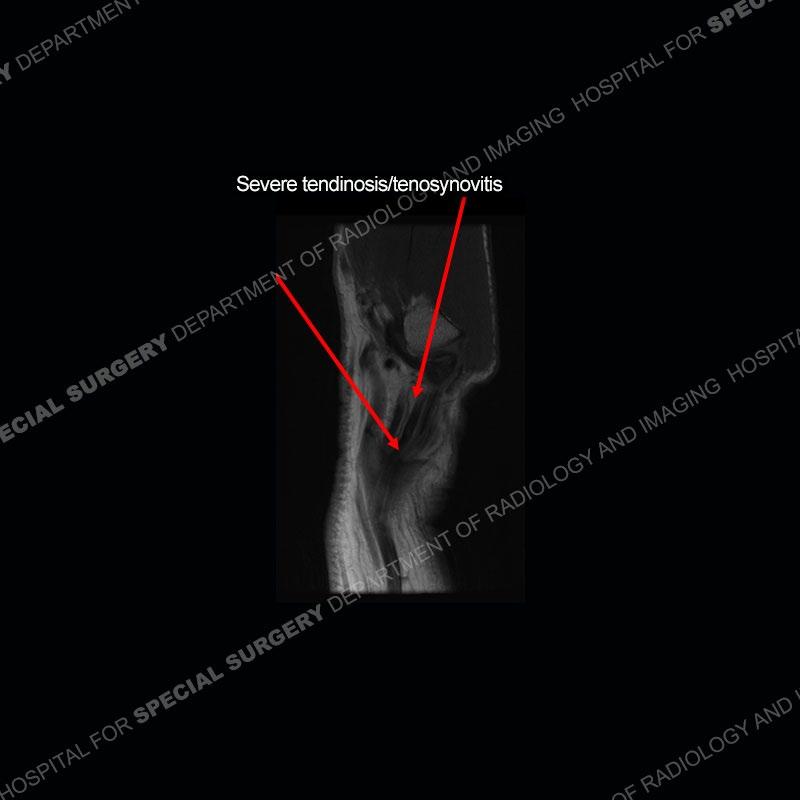

The radiographs in this case are not particularly contributory. The MRI demonstrates tenosynovitis of the first extensor compartment manifest by fluid/synovitis distention of the tendon sheaths. Multiple tendon slips are present of the abductor pollicis longus (APL) and with severe tendinosis seen of one of the tendon slips. Other areas of slightly increased signal and tendinosis are present of the components of the APL. Noted is a somewhat prominent septum separating the more dorsal extensor pollicis brevis (EPB) from the APL.

The first extensor compartment of the wrist contains the abductor pollicis longus or APL (slightly more volar) and the extensor pollicis brevis or EPB (slightly more dorsal). Tenosynovitis of this compartment is known by the eponym of DeQuervain’s tenosynovitis. In addition to tenosynovitis, tendinosis, and partial tearing can be seen. Complete disruption of the tendons is extremely uncommon. More common in women than men, this can affect almost any age patient. It is typically seen in individuals who perform repetitive gripping maneuvers or thumb overuse as can be seen in gripping a golf club or racket. The symptoms are frequently able to be managed with rest and ultrasound guided injections. Recalcitrant cases may require surgical intervention.